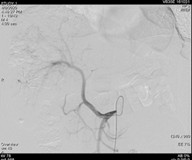

基于mRECIST标准,可判定为一线治疗后疾病进展。遂换用瑞戈非尼联合PD-1单抗治疗。2020年7月6日异常凝血酶原降至49.89 ng/ml。2020年9月17日再次复查,肝增强CT提示,肝脏多发占位性病变,病灶内可见肿瘤存活。病情较前稳定,未见显著进展。

图片

图:肝增强CT(2020-9-17)